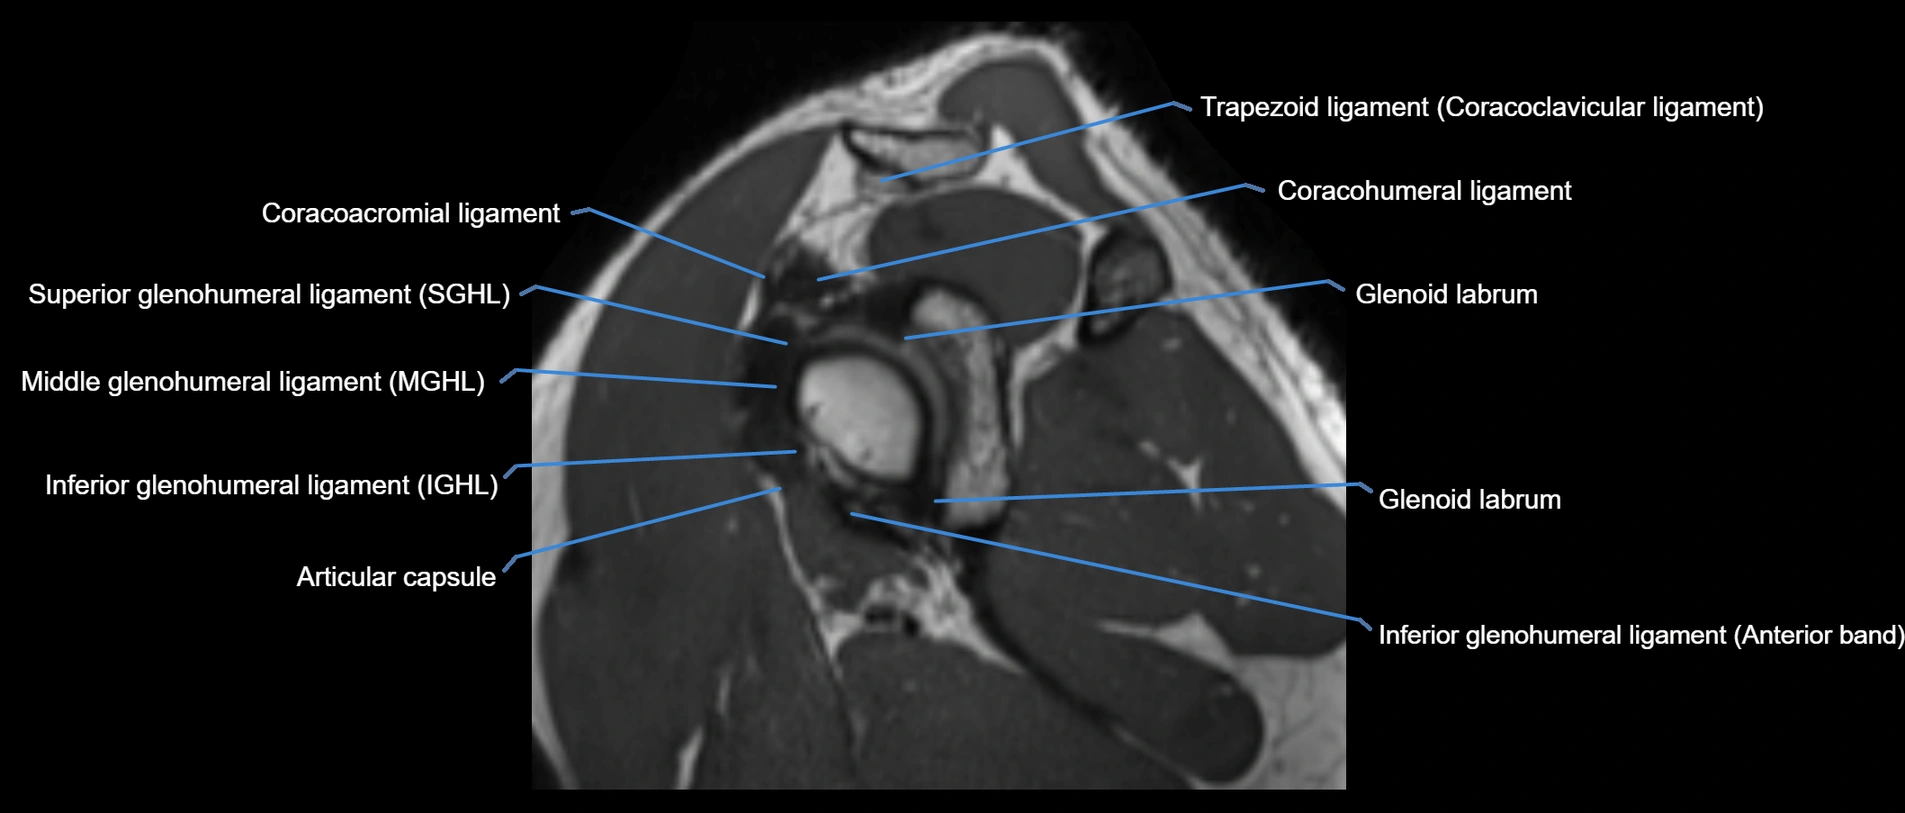

MRI Appearance

• T1-weighted images:

• Normal ligament: Low signal (dark linear band) spanning acromion to clavicle.

• Surrounding fat planes: Bright, delineating the ligament clearly.

• Marrow of clavicle and acromion: Bright due to fatty content.

• Tears: Discontinuity or irregular thickening with intermediate-to-bright signal.

• Chronic injury: Thinning, fraying, or irregular low-signal fibers with adjacent scarring.

• T2-weighted images:

• Normal ligament: Low signal, homogeneous.

• Partial tear or sprain: Focal hyperintensity or thickening.

• Complete tear: Discontinuity with fluid-bright gap between clavicle and acromion.

• Associated edema: Bright signal in distal clavicle or acromion marrow.

• STIR:

• Normal ligament: Dark linear band.

• Injury or inflammation: Bright hyperintense signal in and around ligament fibers.

• Highlights periligamentous soft-tissue edema, especially in acute trauma.

• Proton Density Fat-Saturated (PD FS):

• Normal ligament: Low signal, uniform thickness.

• Partial tear or sprain: Bright signal or contour irregularity.

• Complete tear: Clear discontinuity with bright signal gap and joint effusion.

• Excellent for assessing joint capsule, coracoclavicular ligaments, and periarticular edema.

MRI images

image